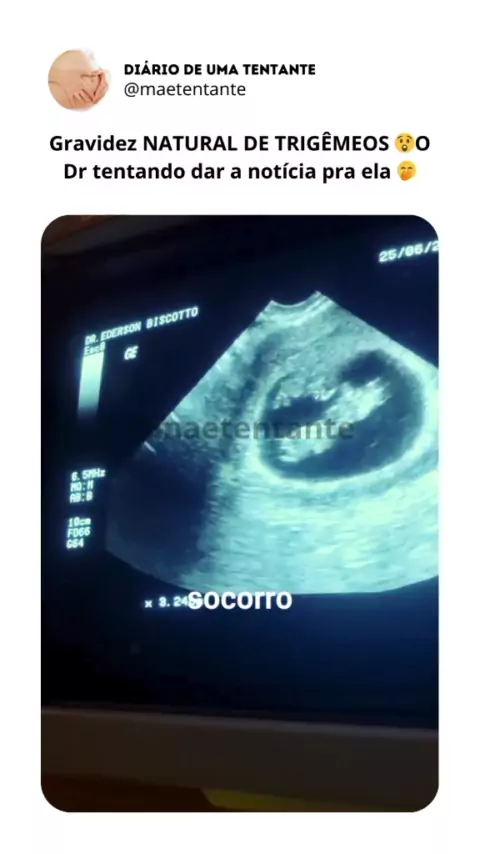

Mãe Tentante ❤️

#trigêmeos #gravidez #gestaçao #maetentante #tentante